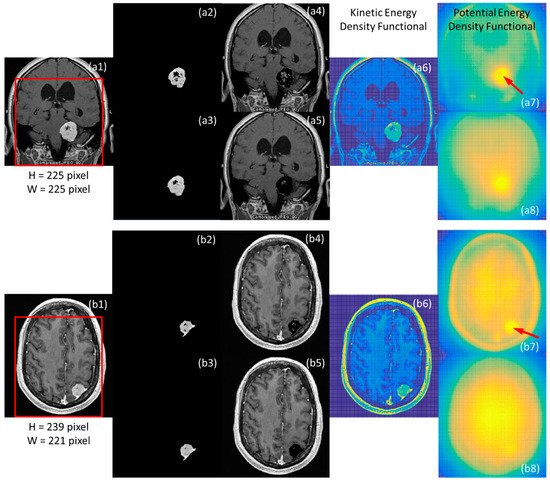

3. Segmentation Results of Brain MRIs and Cell Culturing Images